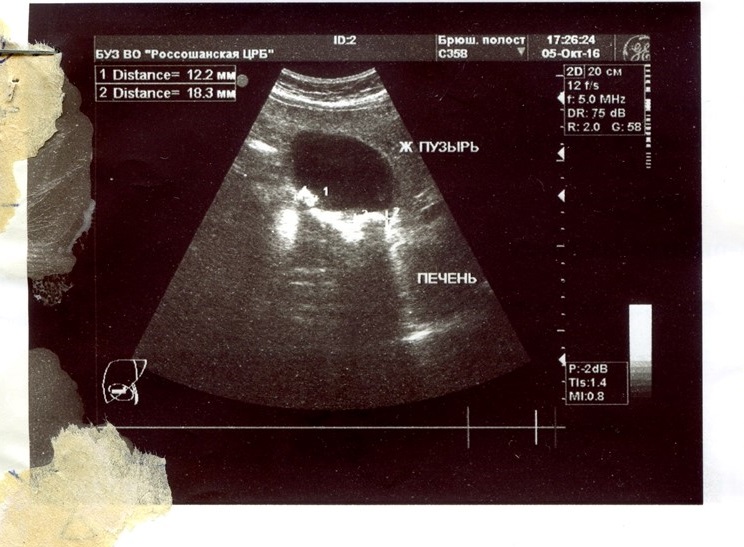

Посмотрите, пожалуйста, когда время будет.

Только получил от отца УЗИ.Klaus » 25 май 2017 10:17 писал(а):bar2ian

Желчнокаменная болезнь от гепса не зависит. Из-за неё нарушается отток желчи, что ведет к разного рода осложнениям в органах БП.

Гастроэнтеролог должен разобраться в проблемах с желчным и назначить лечение (возможно, и хирургическим путем - удаление желчного).

УЗИ можно скинуть в тему и позже.

Трансы могут держаться выше нормы даже из-за камней...

По данному УЗИ я бы не поставила такой высокий фиброз.

Думаю, показатели фиброза были завышены из-за высоких трансов.

С желчным нужно разобраться: можно ли попить УДХК? Образования есть в желчном, но небольшие. Но они могут ухудшать биохимию и самочувствие.

АЛТ и АСТ сдавали после терапии? Когда планируете сходить на фиброскан?

Кстати, УЗИ старое - нужно переделать. За это время могло всё измениться!!

Описания селезёнки нет!! Этот орган нужно исследовать обязательно.